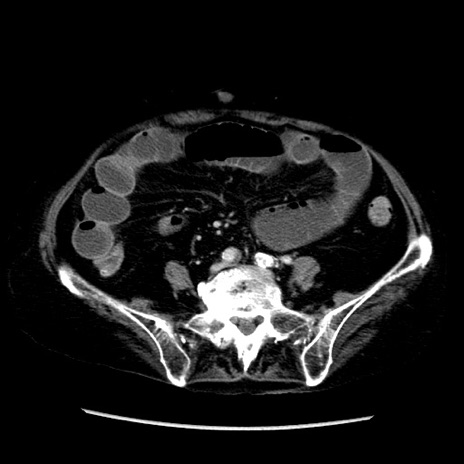

症例14(横断像)

【症例】 90歳代女性

【主訴】 腹痛・嘔吐

【現病歴】今朝から左側腹部痛を認めた。 経過観察していたが、嘔吐を認めたため来院。

【既往歴】 子宮癌術後

【身体所見】 意識清明、BP 127/54mmHg、P 98bpm Sp02 95%(RA)、BT 35.8°C、腹部平坦・軟腸ぜん動音聴取良好、右下腹部圧痛(+) 反跳痛なし

【データ】WBC 9800、CRP 0.46